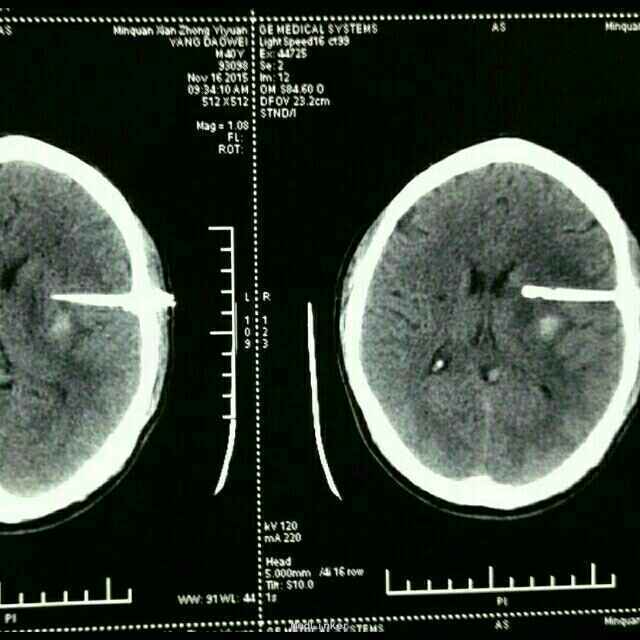

杨XX,男,40岁。 主诉:右侧上下肢无力伴失语15天。 病史:15天前在浙江务工时突然晕倒,随到浙江台州某医院就诊。神志清,精神差,查头颅CT示:“脑出血”,给予保守治疗。15天后家属要求转入原籍我院治疗。转入院时:神志清,精神可,血压:164/98mmHg,失语,右侧上下肢瘫痪,右侧上下肢肌力0级。 既往未检测血压。

诊断:高血压脑出血 治疗:微创钻孔血肿引流术。 术后应用尿激酶溶解血肿,引流顺利。 术后第四天拔除引流管。